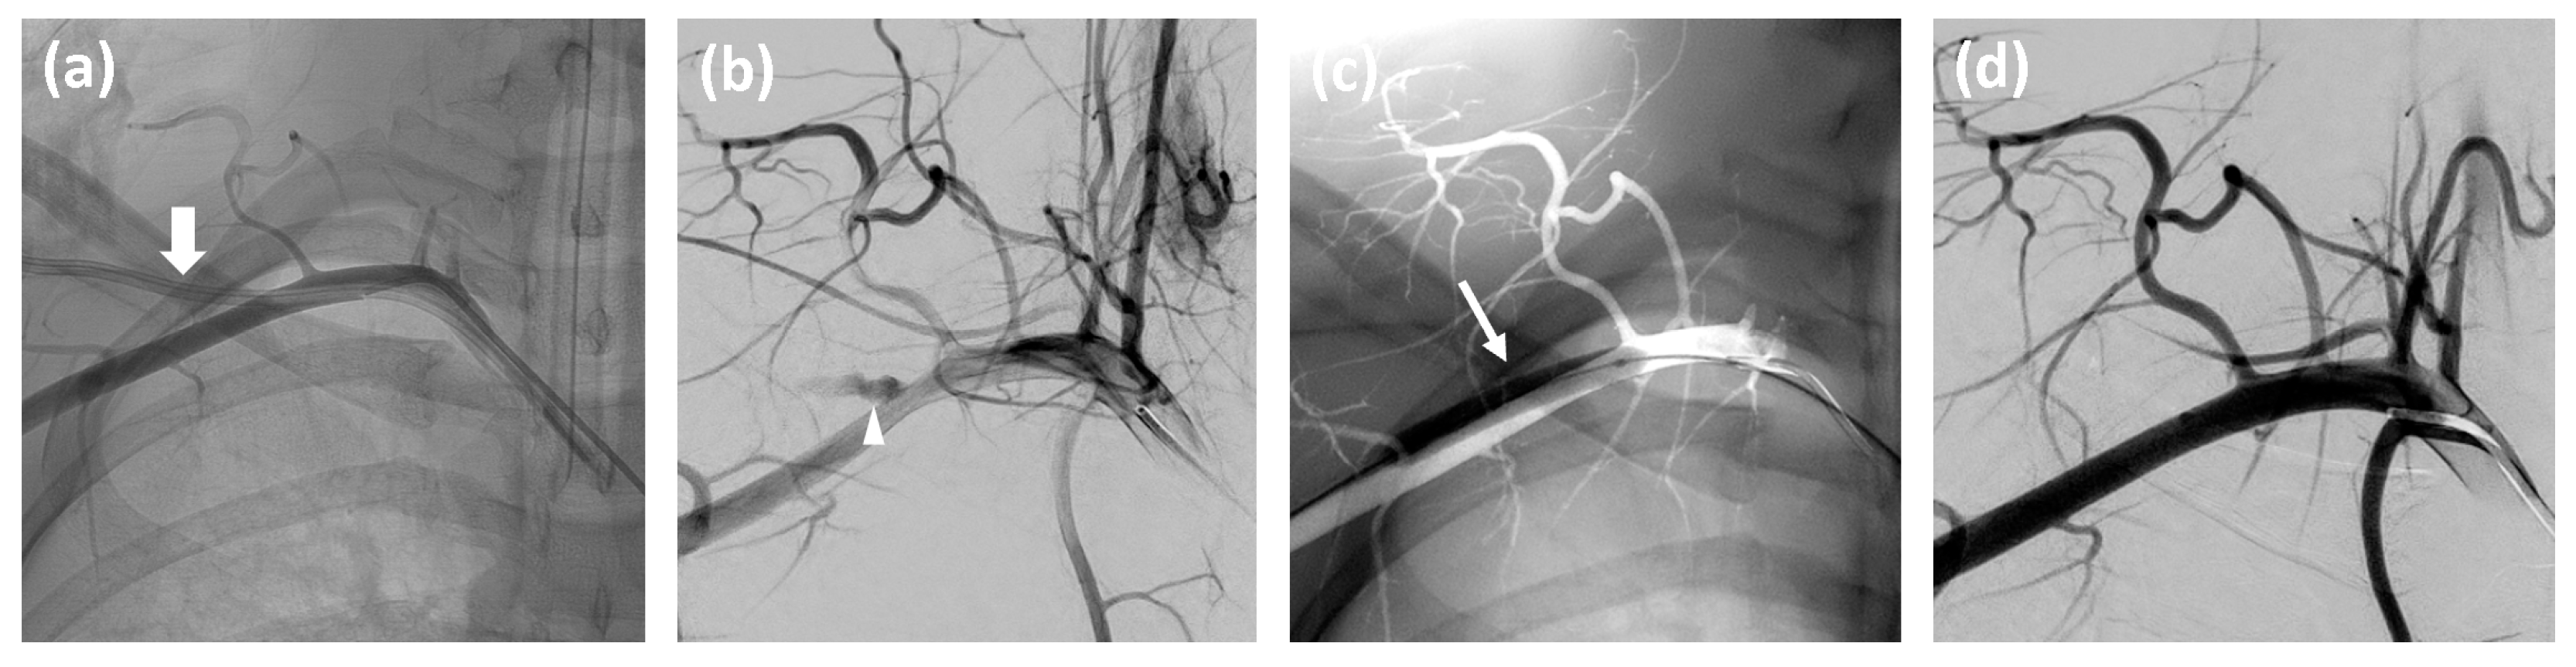

- Establish inguinal arterial access via an ultrasound-guided puncture of the common femoral artery.

- Advance a catheter in the affected subclavian artery and perform angiographic contrast series in at least two projections to visualize the exact position of the misplaced catheter or the presence of any complications such as dissection or hemorrhage.

- Conduct a follow-up angiographic series to confirm successful closure.

- If hemorrhage or pseudoaneurysm is detected, inflate the prepared angioplasty balloon for at least three minutes. For persistent hemorrhage, deploy an appropriately sized stentgraft, taking care to preserve the vertebral artery origin.

- Remove the inguinal access if no complications are observed.